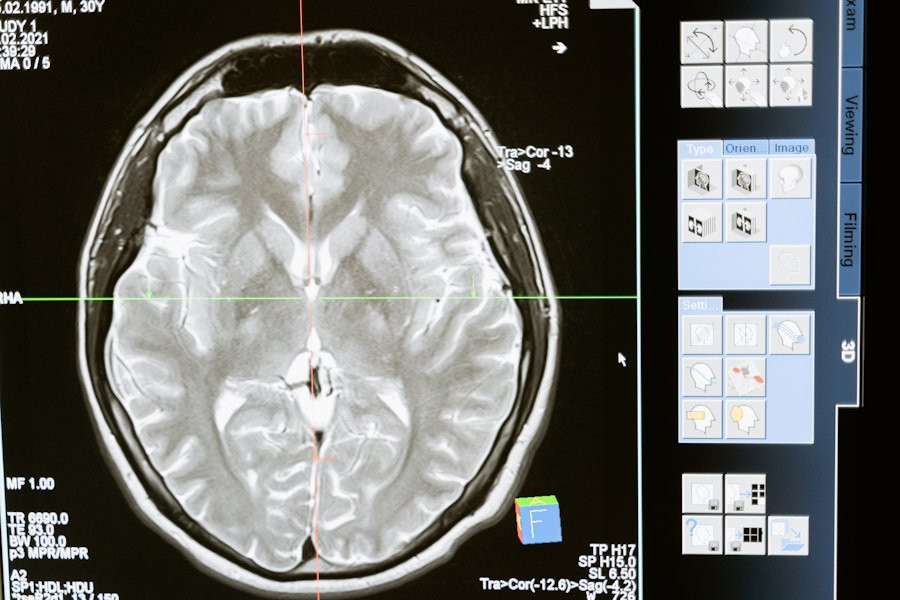

Головной мозг, наша самая сложная "компьютерная" система, подвержен воздействию многих факторов, и его работа остается загадкой. В нем содержится около 100 млрд нейронов, каждый из которых связан с другими посредством синапсов, создавая замысловатую паутину. Мозг способен выполнять операции со скоростью от 1012 до 1028 FLOPS/сек, в то время как самый быстрый суперкомпьютер 2022 года работает с мощностью 1,6 Х 1018 FLOPS/сек, сообщает ТАСС.

Проблемы с мозгом могут проявляться различными способами: от общих симптомов, таких как слабость и головные боли, до конкретных функциональных нарушений, таких как нарушения речи или координации движений. К примеру, недавно "Определены участки генома, связанные с ускоренным развитием деменции".

По данным неврологов, мозг чувствителен к воздействию различных факторов, включая алкоголь и курение, но наиболее вредными являются дефицит кислорода и глюкозы в крови. Нейроны в мозгу зависят от поступления глюкозы через кровь, и при отсутствии кровообращения они начинают умирать в течение пяти минут. Стресс также влияет на мозг, меняя химический баланс и передачу сигналов.